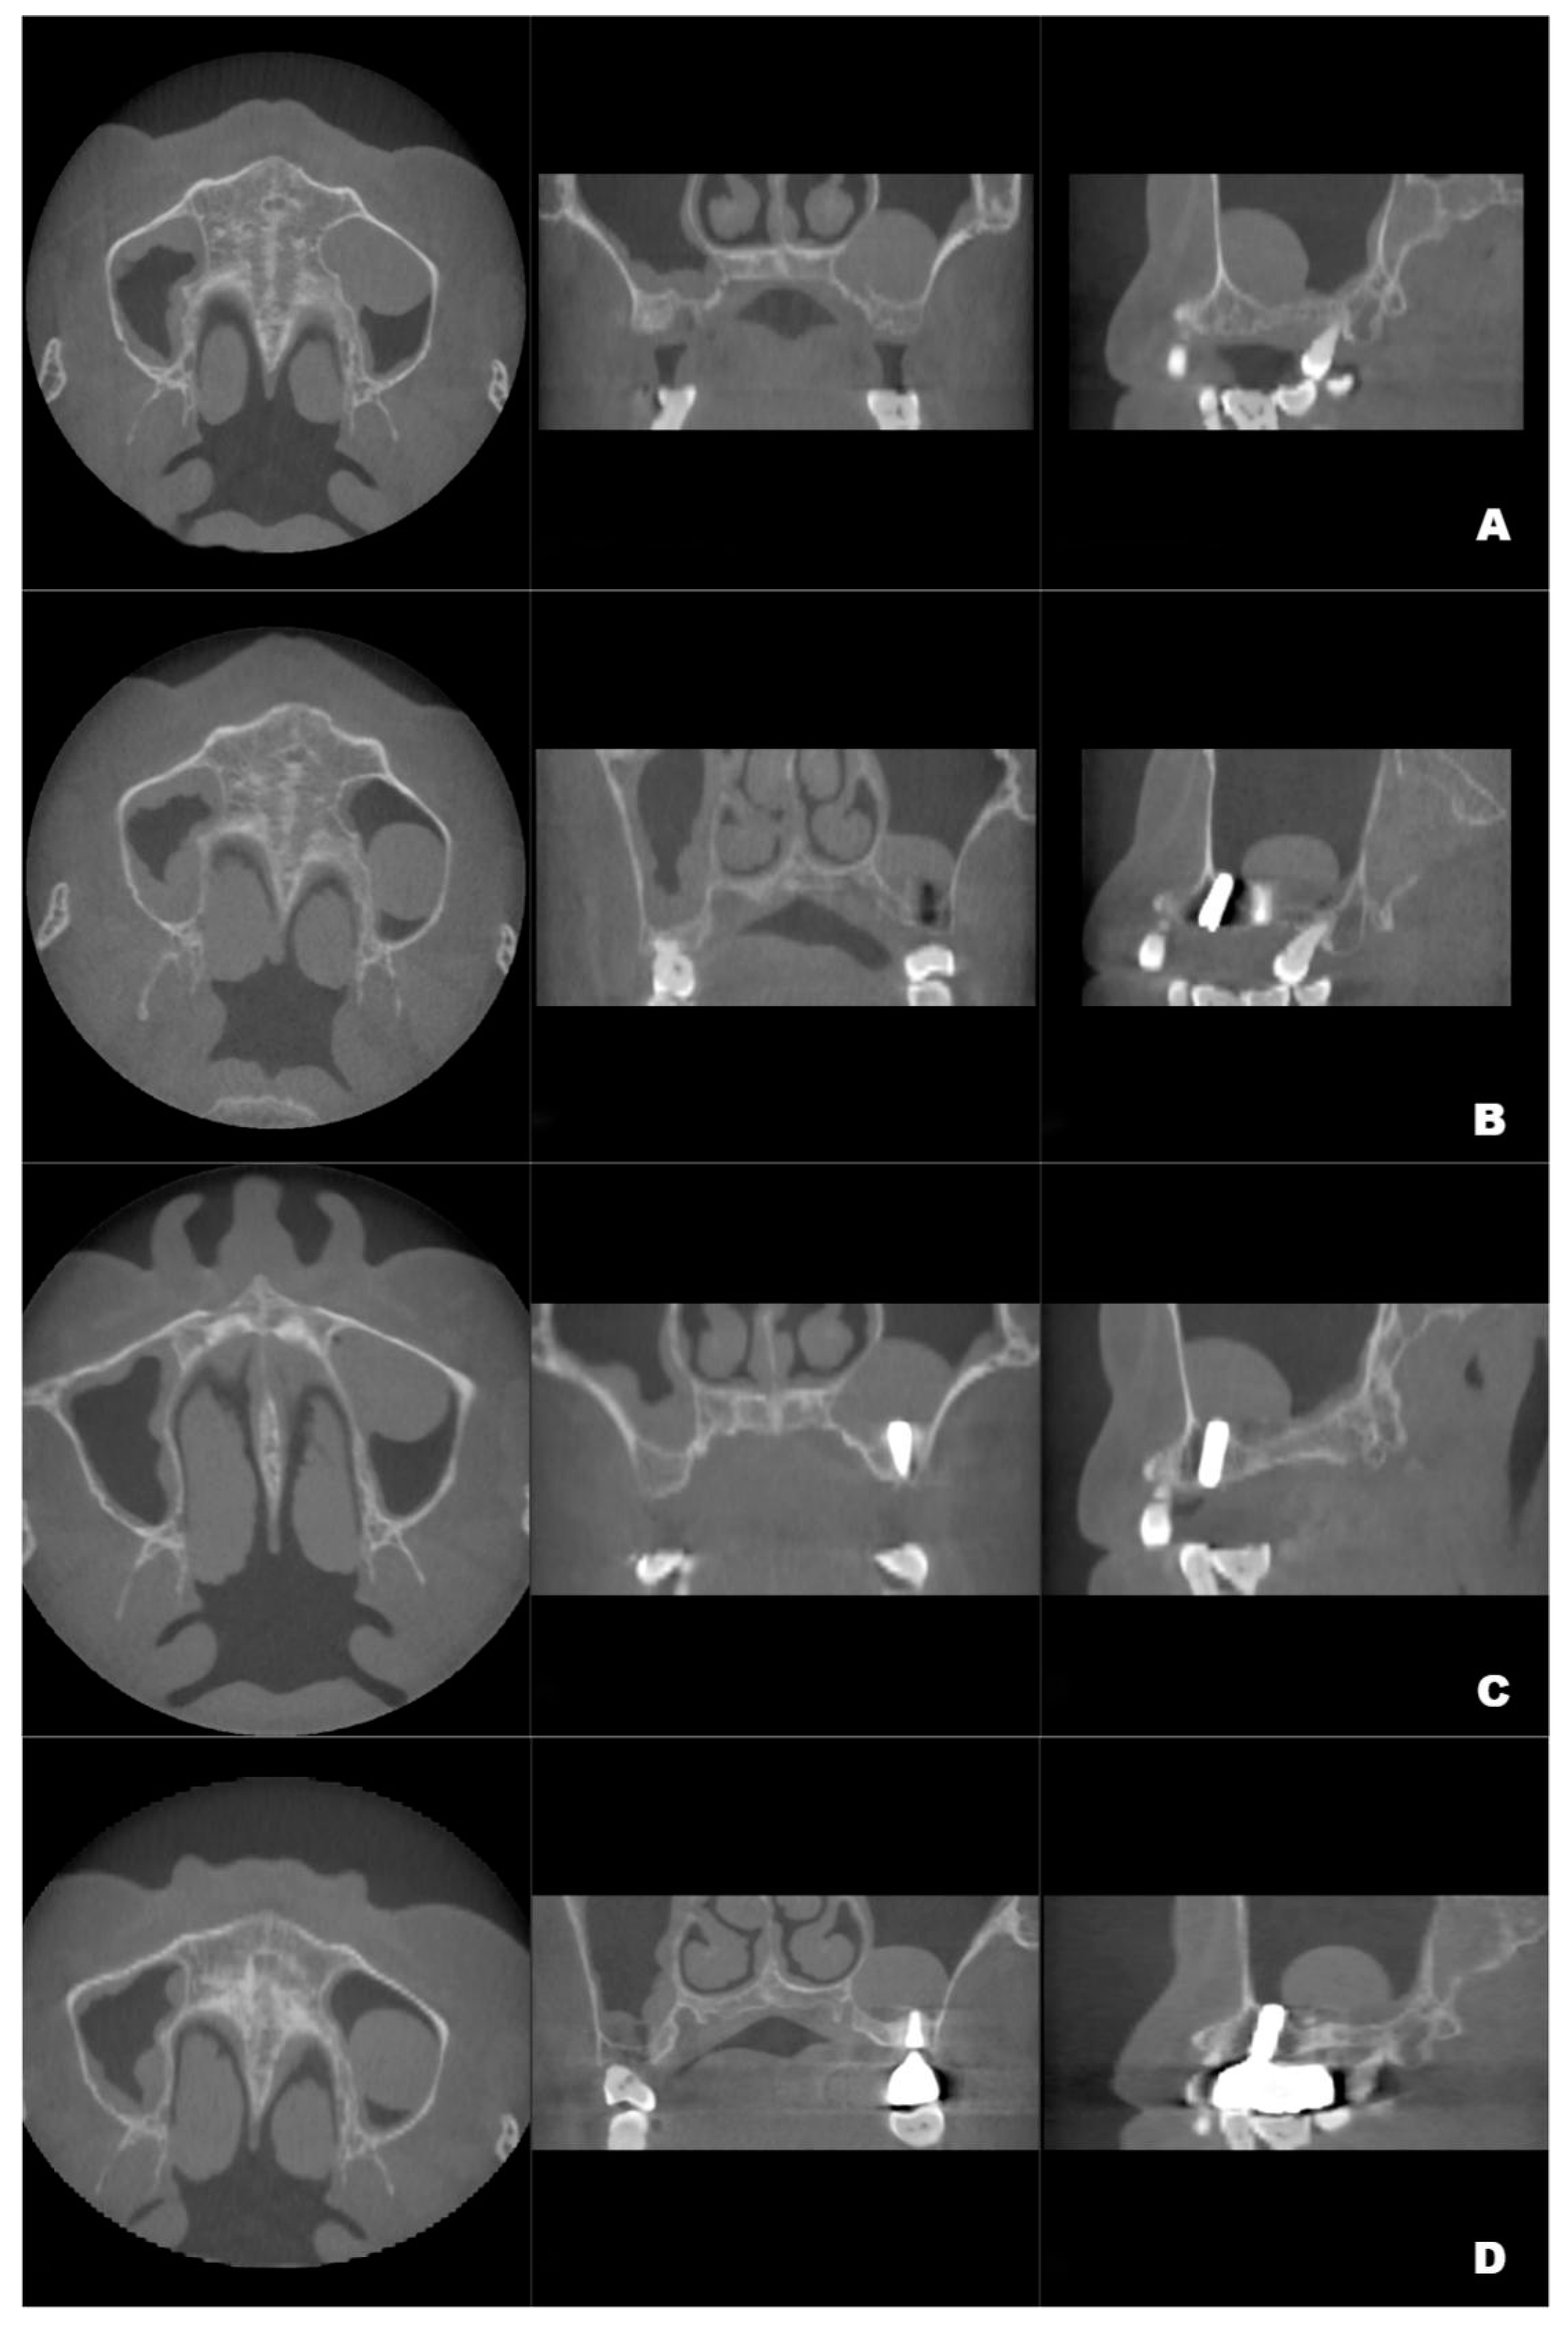

Figure 2.

The volume changes and maximum diameter changes in the axial, coronal and sagittal planes of the patient’s left maxillary antral pseudocyst in the preoperative CBCT image (A) and the follow-up CBCT examinations in 6 (B), 12 (C) and 22 months (D), respectively.

Although the final crown restoration (second procedure) was planned for 6 months after the first procedure, it was delayed until 10 months because of an outbreak of COVID-19. A CBCT scan at the 6-month follow-up showed that the implants had been correctly placed in the augmented sinus, resulting in osseointegration without mobility (Figure 3B). CBCT scans at 12 months and 22 months showed stable bone levels around the implants (Figure 3C,D). The patient reported no discomfort or other complaints in relation to the implants or the maxillary sinus, and no fluid leakage was evident on the incision line during follow-up. However, a comparison of the preoperative CBCT scans with the postoperative scans conducted at 6, 12, and 22 months revealed pseudocyst drift in the left maxillary sinus (Figure 4). At 6 months after surgery, the pseudocyst had moved posterolaterally from the preoperative position near the anterior medial maxillary sinus, then returned to its original position at 12 months. However, it had remigrated to the posterolateral position at 22 months.

Figure 3.

Preoperative CBCT (A) and follow-up CBCT images (6 months (B), 12 months (C), and 22 months (D)) of the patient’s left maxillary antral pseudocyst in the axial, coronal, and sagittal planes.

The pseudocyst volume was manually segmented using 3D Slicer and corrected by a professional radiologist [19]. Measurements of the maxillary sinus pseudocyst revealed that its volume decreased from 3.795 mm3 before surgery to 2.370 mm3 at 6 months post-surgery; it gradually returned to the preoperative volume at 12 months (3.439 mm3), then decreased to 2.930 mm3 at 22 months (Figure 2).